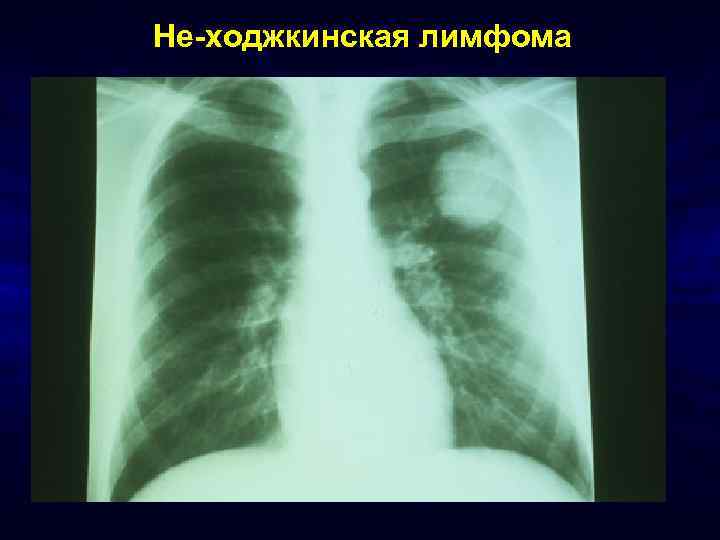

Не-ходжкинская лимфома

Рак легких • В теч. последних лет частота рака легких возросла среди пациентов с ВИЧинфекцией в 2 -4 раза ü Kanmogne GD. Non-infectious pulmonary complications of HIV/AIDS. Curr Opin Pulm Med 2005; 11(3): 208212